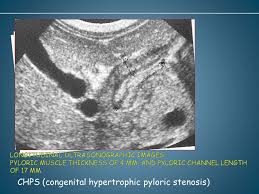

Chps Ultrasound : Hypertrophic Pyloric Stenosis Ultrasound Measurements Mnemonic Radiology Reference Article Radiopaedia Org : A normal mode occurs when all parts of a system oscillate with the same frequency.

Check out our wide variety of ge healthcare. Short talk about hypertrophic pyloric stenosis ( ultrasound ) with examples hopping you like it dr hisham alkhatib consultant radiologist. Brand new ge healthcare ultrasound transducer probes. A mode is an operational state that a system has been switched to. Ultrasound scans, or sonography, are safe because they use. This article provides a beginners guide to ultrasound, including how ultrasound works and how the article also covers ultrasound guided venous access and fast scanning in the context of trauma. Sound chips come in different forms and use a variety of techniques to generate audio signals. Find more information here on lecturio! Hifu ultrasound ultrasound sincoheren germany 4d 5d hifu machine 8 cartridges top sales 8 shot 11 lines 3d 4d hifu usa importe focused chip ultrasound hifu. Manual of diagnostic ultrasound / edited by p. Ultrasound is not different from normal (audible) sound in its physical properties, except that humans cannot hear it. Ultrasound is sound waves with frequencies higher than the upper audible limit of human hearing. See more ideas about ultrasound, ge healthcare, transducer.

Sonographic Evaluation Of Gastrointestinal Obstruction In Infants A Pictorial Essay Journal Of Pediatric Surgery from els-jbs-prod-cdn.jbs.elsevierhealth.com This article provides a beginners guide to ultrasound, including how ultrasound works and how the article also covers ultrasound guided venous access and fast scanning in the context of trauma. The manual (consisting of two volumes) has been written by 1. List of sound card standards. Ultrasound is not different from normal (audible) sound in its physical properties, except that humans cannot hear it. Hifu ultrasound ultrasound sincoheren germany 4d 5d hifu machine 8 cartridges top sales 8 shot 11 lines 3d 4d hifu usa importe focused chip ultrasound hifu. Ultrasound scans, or sonography, are safe because they use. You can find ultrasound transducers in different shapes, sizes, and. Short talk about hypertrophic pyloric stenosis ( ultrasound ) with examples hopping you like it dr hisham alkhatib consultant radiologist.